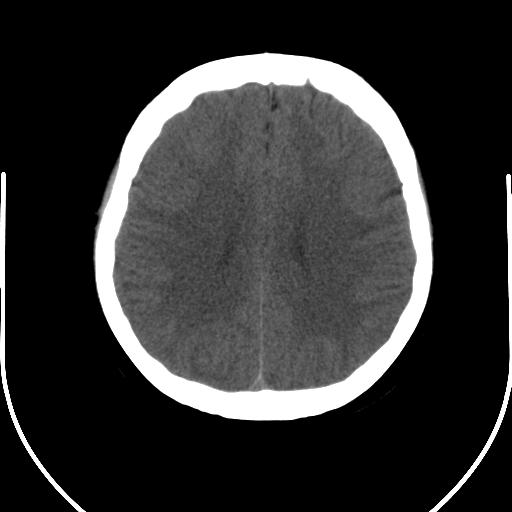

以下是引用mlxq3086在2007-8-27 13:35:00的发言:[br]单凭平扫无法诊断,请结合增强了解!